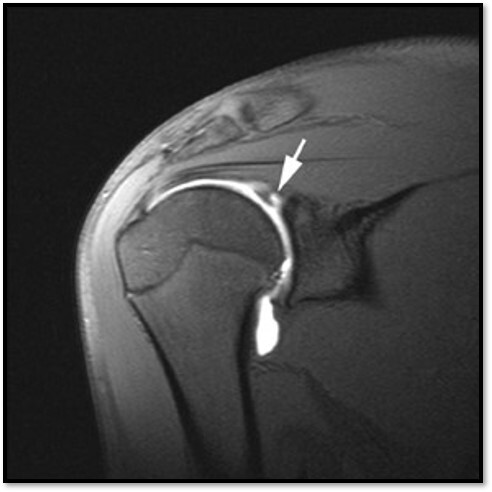

What is this showing?

A

MR Shoulder with Contrast

What is an example of a pathology that requires MRI contrast?

A Labral tear in the shoulder

32

What contrast must be given for pathologies that cannot be seen on MRI without it?

Iodinated contrast and gadolinium mixed